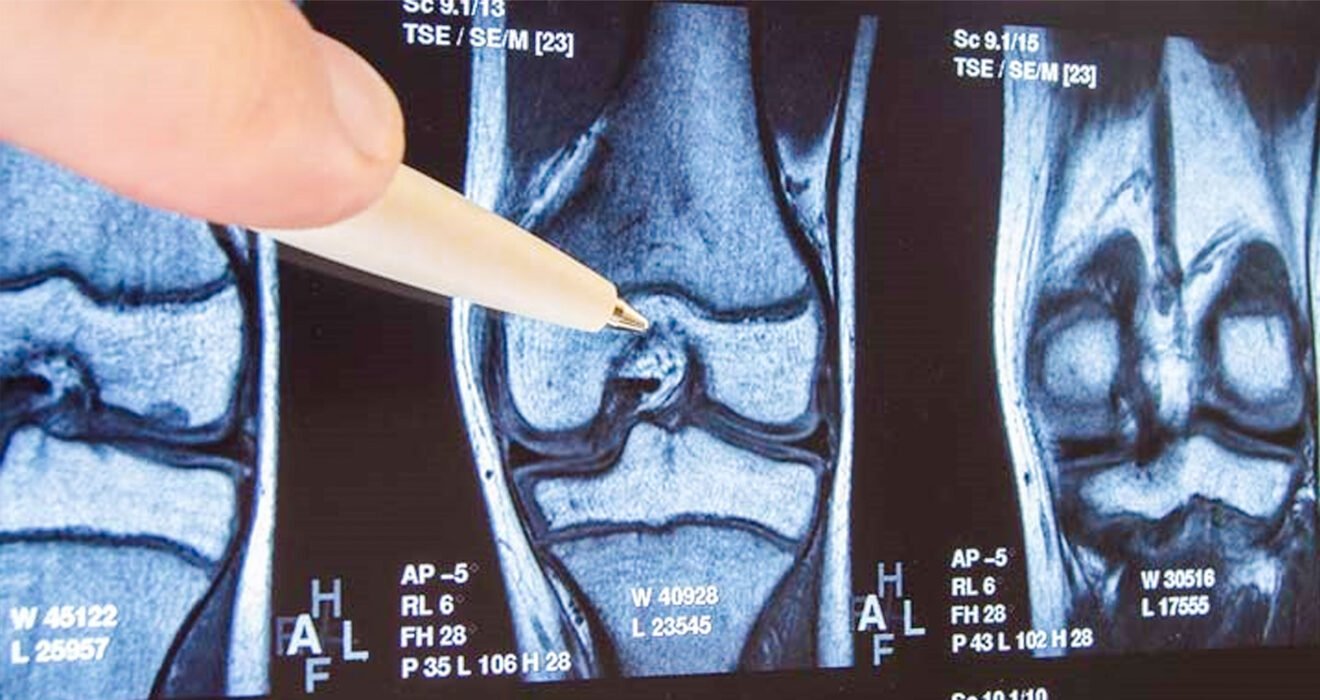

The Rising Tide of Knee Osteoarthritis in the Workforce

Knee osteoarthritis (OA) is becoming increasingly prevalent among the working-age population. The number of total knee replacements (TKRs) performed on individuals under 68 years old has risen significantly, with a 188% increase observed between 2000 and 2015 (AAOS, 2014). This trend is attributed to rising obesity rates, sedentary lifestyles, an ageing workforce, and increased physical demands in certain occupations.